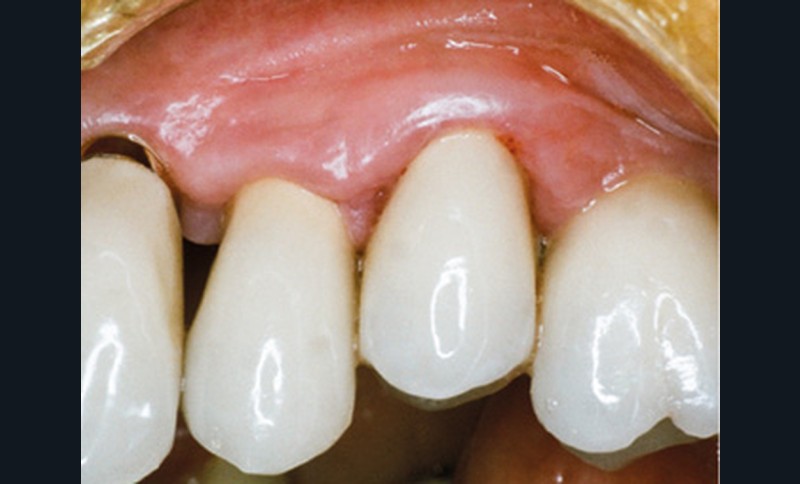

En mars 2016, la patiente se plaint d’une sensibilité sur la 25 et on note cliniquement une inflammation gingivale associée à un décalage apical du rebord marginal et de la ligne muco-gingivale en comparaison de leur situation visualisée au niveau des coiffes supra-implantaires. La couronne clinique est réduite et une infraposition avec une inocclusion d’environ 2 mm par rapport au plan d’occlusion et aux dents antagonistes est également notée (fig. 2 à 4). Un saignement au sondage ainsi qu’une poche de 5 mm en distal sont constatés. Le test de percussion est positif. Les tissus péri-implantaires adjacents ne présentent aucun signe de mucosite.